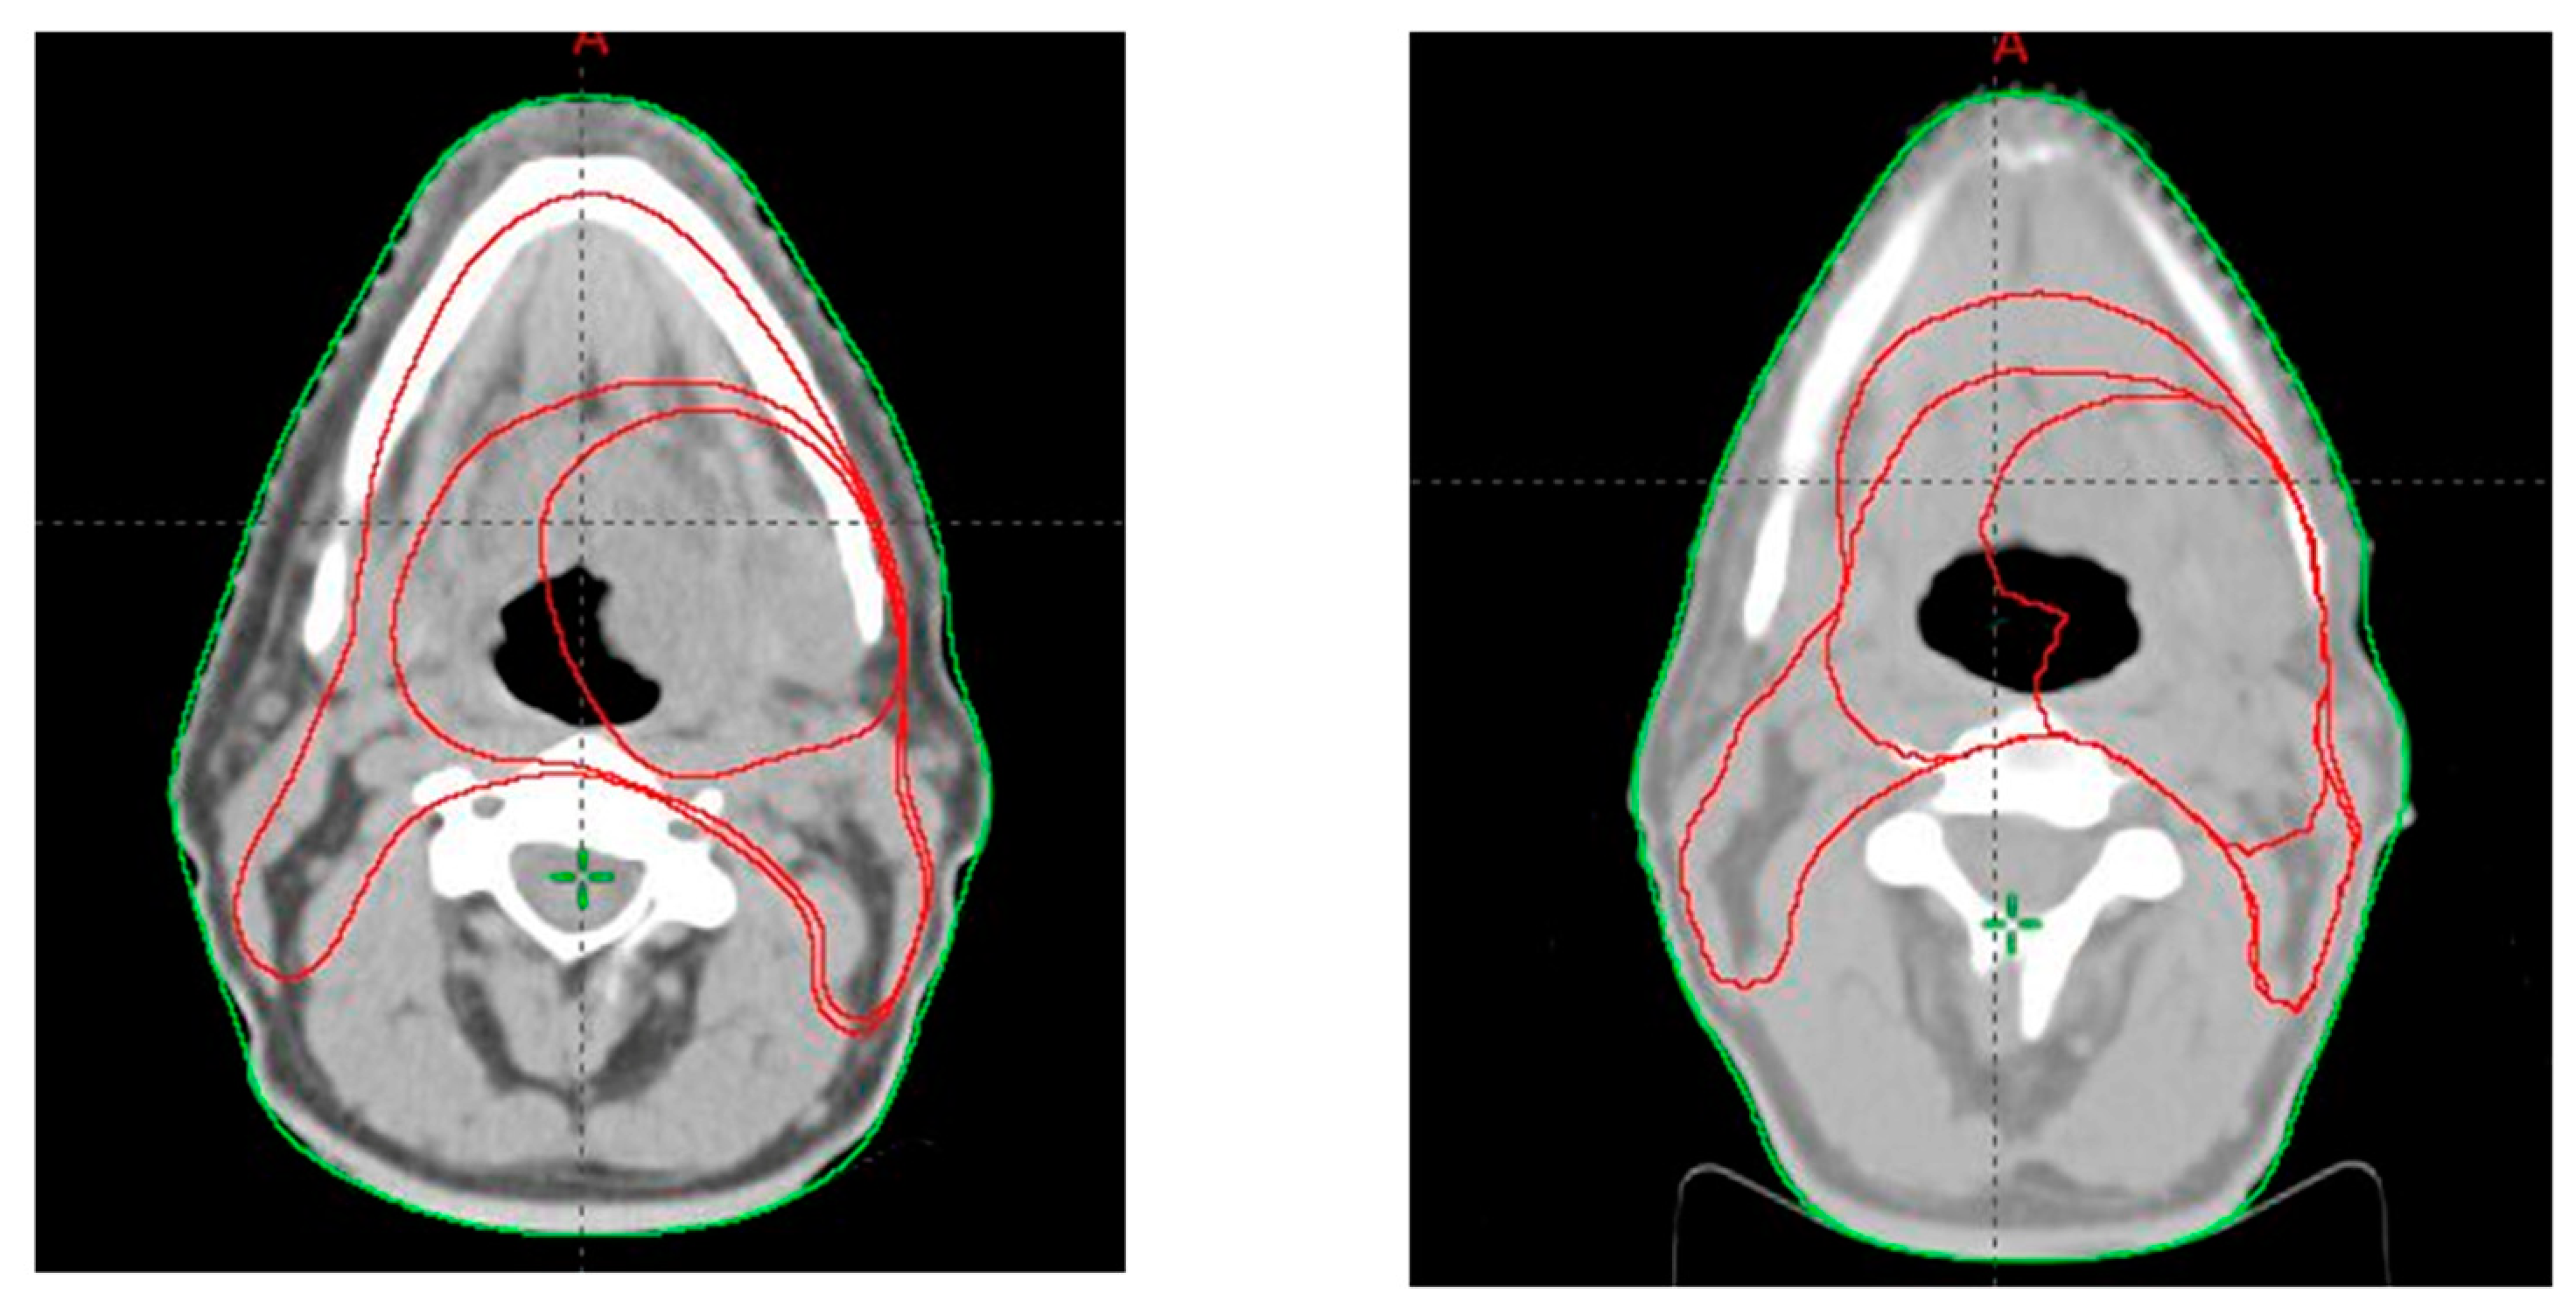

2.2. Target Volume Delineation

3.1. PTV Shrinkage

3.2. Parotid Glands Shrinkage

3.3. Dosimetry of Organs at Risk